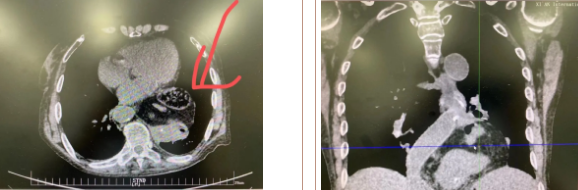

據(jù)了解,患者多年來進(jìn)食后出現(xiàn)惡心、嘔吐,卻未到醫(yī)院進(jìn)行檢查。3個(gè)月前患者突然出現(xiàn)無尿,全身腫脹等情況才前往就醫(yī),卻遭多家醫(yī)院拒收,輾轉(zhuǎn)來到我院就診。檢查發(fā)現(xiàn)患者已患宮頸癌、進(jìn)而引起腎后性腎衰、同時(shí)合并膈疝、出現(xiàn)泌尿道感染,病情及其復(fù)雜。

經(jīng)泌尿外科積極救治,患者腎衰癥狀緩解,隨后轉(zhuǎn)入放射治療中心進(jìn)行宮頸癌根治性放療。放療期間,患者惡心、嘔吐癥狀逐漸加重,后期無法進(jìn)食,排除機(jī)械性腸梗阻和放療因素,考慮因長期膈疝加重引起,經(jīng)胸外科會診后轉(zhuǎn)入胸外科一病區(qū)準(zhǔn)備手術(shù)治療。

麻醉手術(shù)中心副主任丁倩為減輕患者術(shù)后不適,實(shí)施單腔聯(lián)合支氣管封堵插管,同時(shí)進(jìn)行了肋間神經(jīng)阻滯麻醉。術(shù)中發(fā)現(xiàn)患者膈疝巨大,食管和疝囊分界不清,部分胃組織和結(jié)腸疝已進(jìn)入胸腔。李文海憑借豐富的臨床經(jīng)驗(yàn),仔細(xì)辨別解剖變異,有序完成分離、縫合、修補(bǔ)等一系列操作,胸外科穆強(qiáng)副主任醫(yī)師、劉歡住院醫(yī)師、麻醉手術(shù)中心團(tuán)隊(duì)通力配合,手術(shù)最終順利完成,患者安全返回胸外科監(jiān)護(hù)室病房。目前患者術(shù)后恢復(fù)良好,于近日準(zhǔn)備出院。